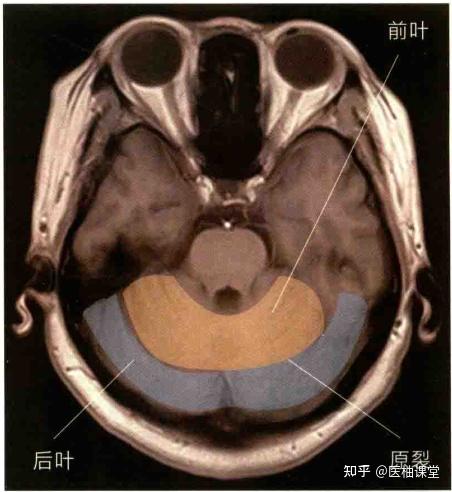

颅脑横断层标本及ct解剖